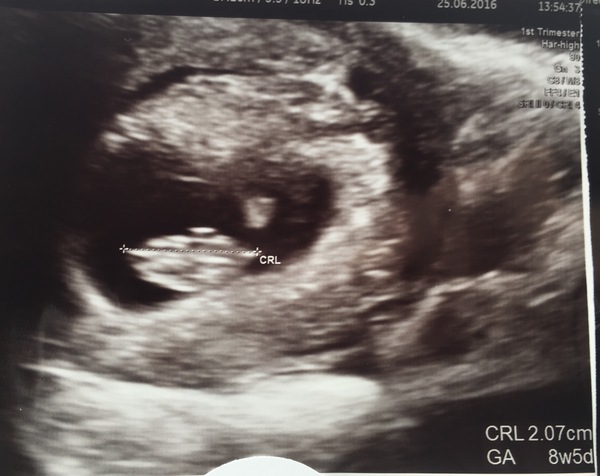

Just been for my private scan. All ok & baby measuring dead on my dates 8+5. Heard the heartbeat too....sounded like a train :-)

Readyfortwo · 25/06/2016 14:21

Here's the pic

Omg Ready that is AMAZING!!! SmileSmileSmileSmile a little baby train Smile